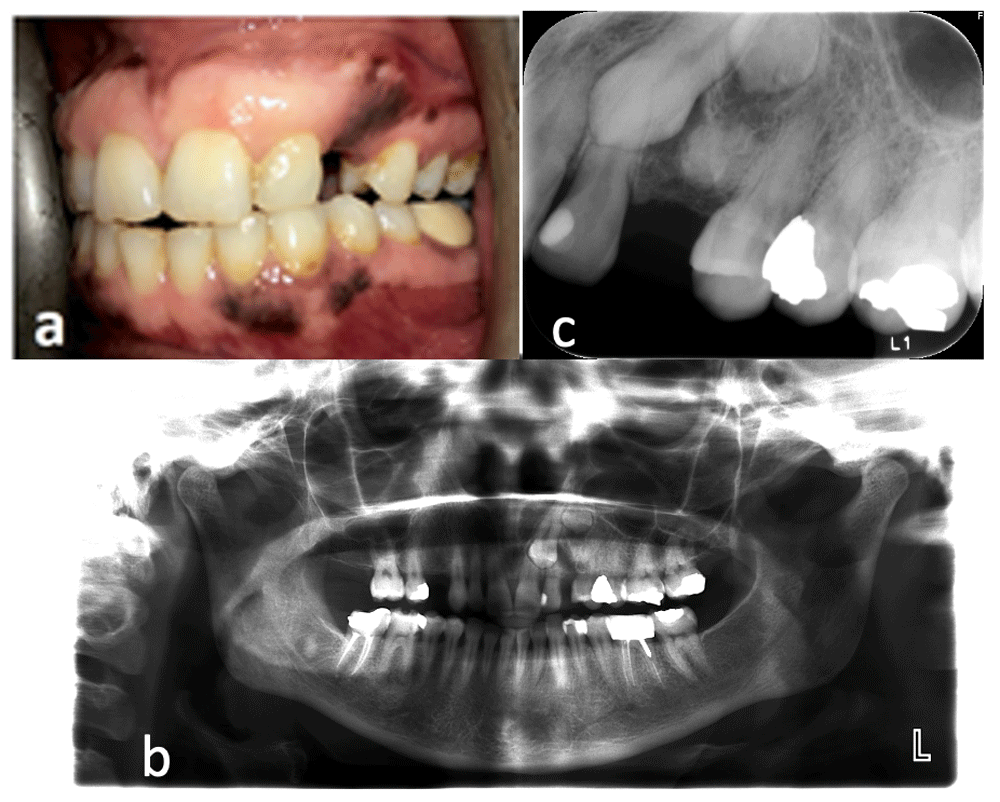

A 47-year old house wife – of African origin - presented to the dental clinic to treat multiple carious teeth, and to replace multiple missing teeth. On Intraoral clinical examination, both the maxillary canines were missing as well as the third molars, and there was a bulge on the buccal cortex of the missing maxillary left canine, which was asymptomatic (Figure 1a). The patient's medical history showed no previous incidence of dental/maxillofacial trauma or infections. She was referred to the Oral and Maxillofacial Surgery clinic for management. Panoramic radiograph revealed the presence of an impacted maxillary left canine and two small radiopaque masses distal to the impacted canine (Figure 1b) and the periapical radiograph showed that the apical mass is a supernumerary tooth and the coronal mass is a rounded denticle like mass (Figure 1c).

a) preoperative clinical intraoral photo showing buccal bulging opposite to the area of impacted left maxillary canine. b) preoperative panoramic radiograph showing impacted left maxillary canines and two radiopaque masses distal to it. c) preoperative periapical radiograph showing impacted canine, supernumerary tooth and radiopaque mass.